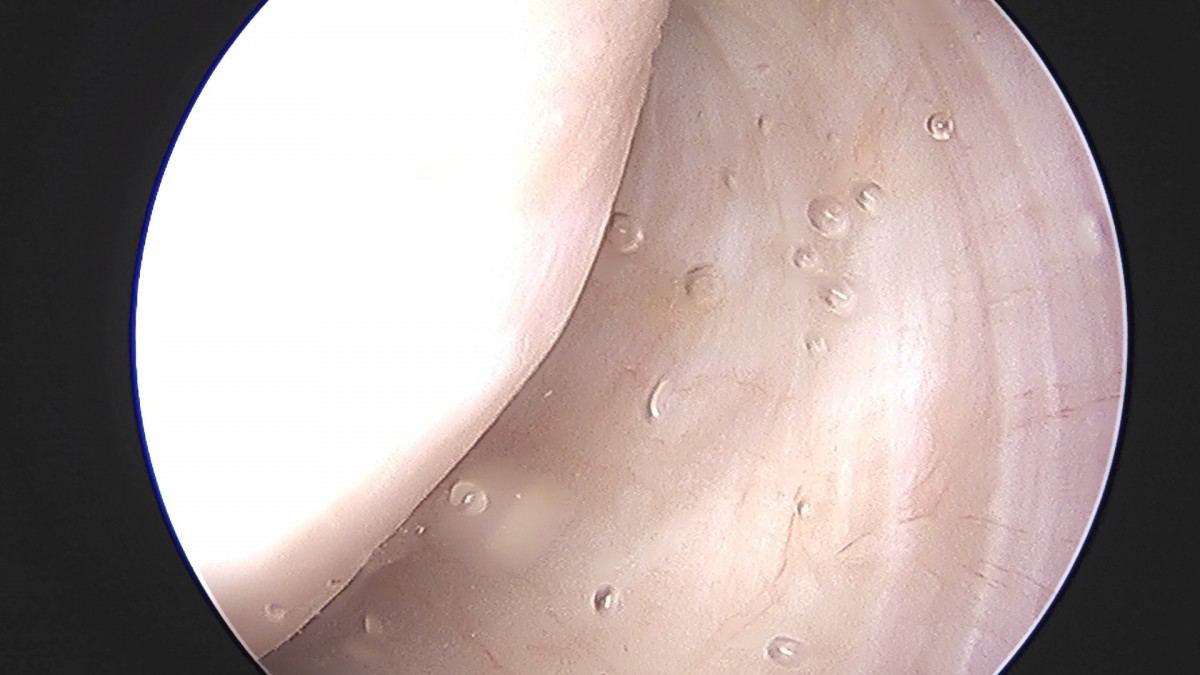

정지영원장님 어깨 회전근개 봉합술 김영O 환자

dae765e4d9ac96aee867c9d6292d8784_1758009061_02.jpg